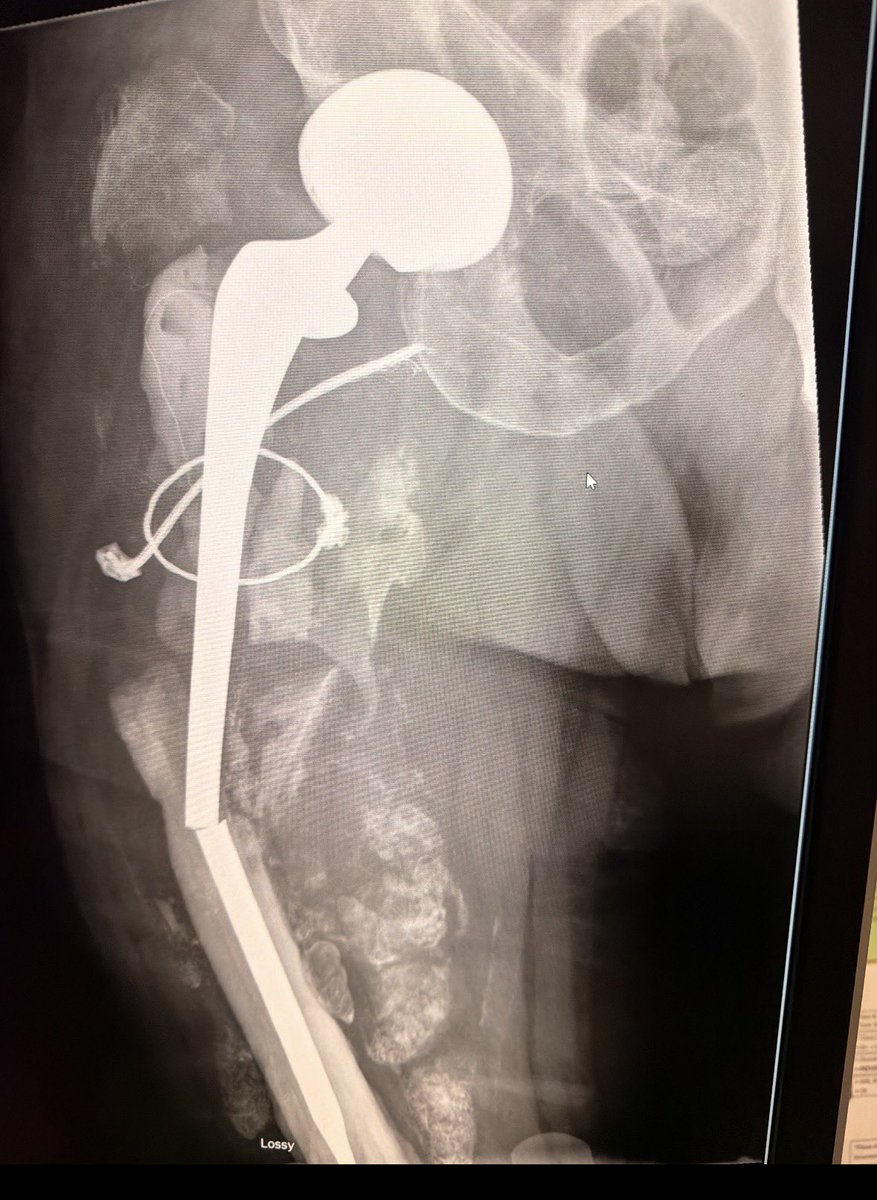

*I know it’s a Sigma RP but that DepuyTeflonTech™️ coating don’t lie